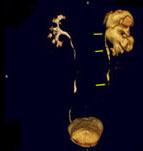

问题 男,58岁,尿频,尿痛伴低热乏力2月,CT如图所示,下列说法正确的是 ( )

选项 A、左侧输尿管结核 B、左侧输尿管癌 C、左侧输尿管多发性狭窄 D、左侧肾结核 E、左侧肾盂肾盏扩张,其边缘不整

答案 ACDE